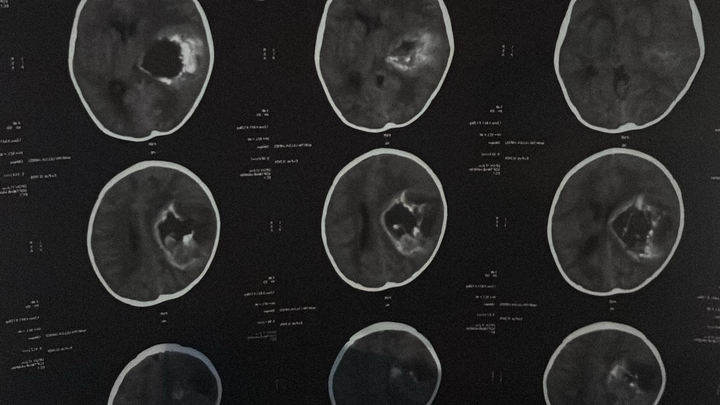

Our sweet 1-year-old has been diagnosed with a massive brain tumor affecting nearly half of his brain.

He suddenly became unresponsive, and doctors discovered a large tumor in the right side of his brain causing dangerous swelling and pressure. He had to be intubated to protect his breathing and is currently fighting for his life.

Nuestro bebe de solo 1 año fue diagnosticado repentinamente con un tumor cerebral muy grande que afecta casi la mitad de su cerebro. El tumor provocó una inflamación severa y una presión peligrosa en su cerebro, y dejó de responder. Los médicos tuvieron que intubarlo para proteger su vida.